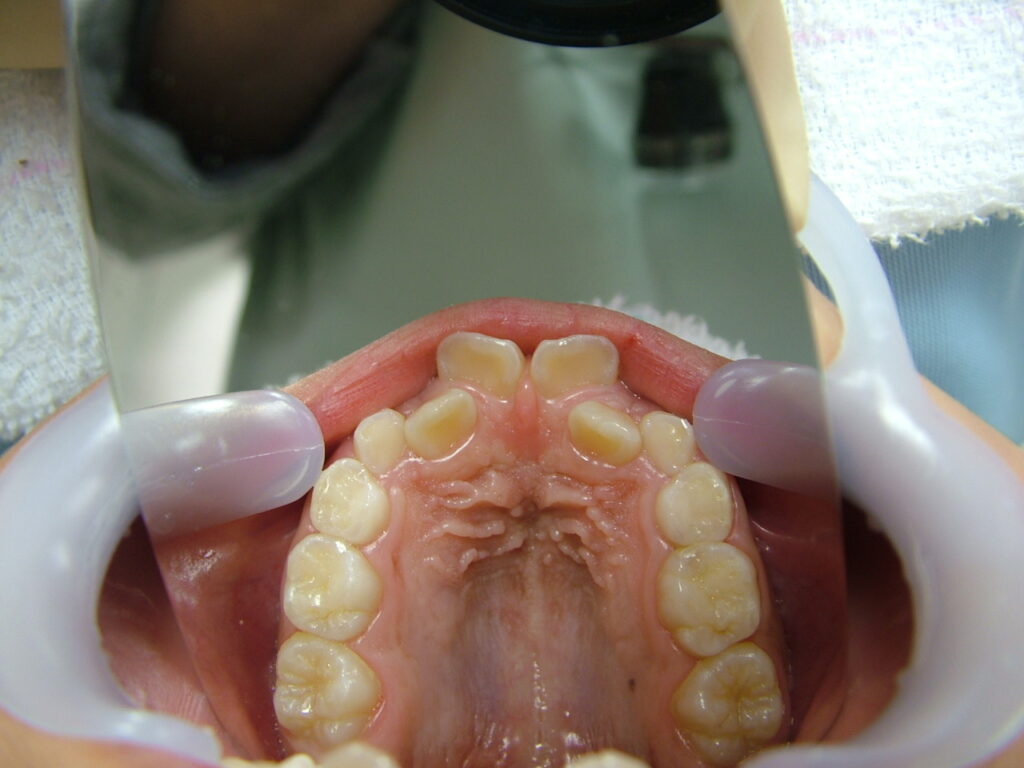

治療後

治療後のコメント

虫歯や歯肉炎の発症なく、まずまずの状態で1期治療を終了したと思います。もう少し上下顎拡大も考えましたが口が大きくなることを考慮して、最小限のディスキングで対応しました。親御さん、子供さん共に非抜歯での矯正を希望されましたが、今後シャープな口元を希望される場合、矯正の専門医で小臼歯4本抜歯ワイヤー矯正されるのも良いかもしれません。しかし舌房が狭くなり、噛みしめが誘発された方(歯周病の悪化、肩こり、知覚過敏、不定愁訴等)を数多く見てきているため、私は成人抜歯矯正(2期治療)をやるつもりはありません。(注、私は全ての抜歯矯正を否定しているわけではありません。正しく舌房の確保、舌のポジション、上下7番のコントロールを考えた矯正医が行うのは素晴らしいと思っています。)